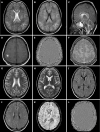

Background: Acute hemorrhagic leukoencephalitis (AHLE), also known as Weston-Hurst syndrome, is a very rare and fulminant form of demyelinating disorder. It is considered a hyperacute and severe variant of acute disseminated encephalomyelitis. Clinically, patients present with fever, headache, seizures, and altered sensorium, which can rapidly progress to coma or death. Magnetic resonance imaging (MRI) is the investigation of choice and plays a pivotal role in diagnosing AHLE. The purpose of this article is to make readers familiar with the typical MRI features of AHLE and to discuss differentials.

Case summary: This case series reports the clinical presentation and typical neuroimaging findings in four patients diagnosed with AHLE. All patients presented with acute neurological symptoms, such as severe headaches, seizures, and altered consciousness, often following a history of fever suggesting an infectious etiology. Additionally, laboratory investigations demonstrated elevated levels of serum inflammatory markers and neutrophilic pleocytosis on cerebrospinal fluid analysis, supporting a post-infectious etiology. MRI findings consistently revealed characteristic white matter lesions with hemorrhagic foci and vasogenic edema, indicative of widespread demyelination characteristic of AHLE. The outcomes varied, with two patients surviving but experiencing neurological sequelae, while two others unfortunately succumbed to the disease. The clinical data, laboratory results, and imaging findings from this case series were systematically compared with those from previously published studies. The key similarities and differences in clinical presentation, imaging characteristics, and outcomes are presented in a tabulated format.